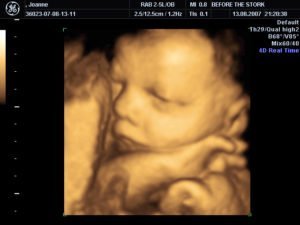

Моя близка е била на фетална морфология в София и снимките които са и дали са от този тип който прикачвам, извинете ме за глупавите въпроси, но съм нова в това.